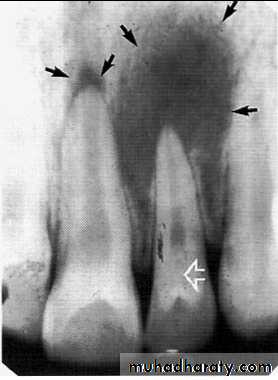

The radiograph shows erosion of the alveolar bone (o) and elevation

of the floor of the nasal fossa (arrows).• Globulomaxillary Cyst

• Located between the lateral incisor & cuspid teeth, the teeth are vital . Radiographically;an inverted• pear shape radiolucency

• between the roots of lateral & cuspid teeth, the roots of teeth pushed apart.

• Treatment by excision.